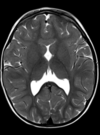

10

30 anos

Esclerose múltipla